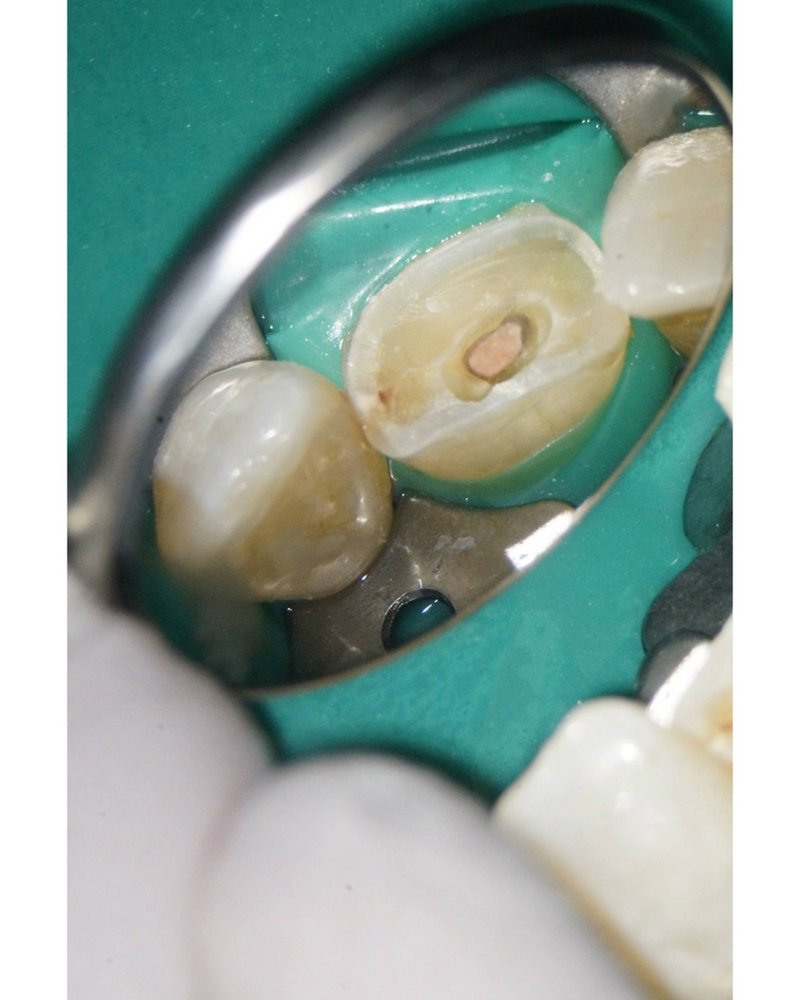

Wurzelkanal gefüllt in Continuus Wave Technik und Backfill, dargestellt unter dem Mikroskop